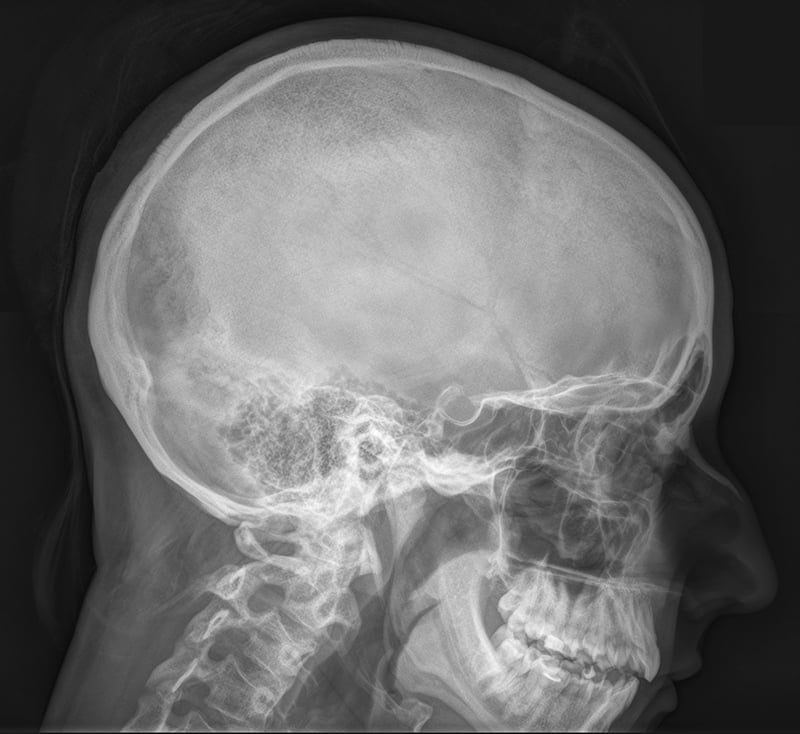

Диагноз устанавливается при осмотре пациента, выслушивании его жалоб и изучения анамнеза. Косвенным подтверждением служит наличие у больного суставных или эндокринных патологий. Симптомы височного тендинита очень схожи с клиническими проявлениями воспаления тройничного нерва и обострения артрита или остеомиелита височно-челюстного сустава. Для дифференцирования заболеваний проводятся инструментальные исследования:

- компьютерная или магнитно-резонансная томография;

- электрорентгенография.

Ультразвуковое исследование необходимо для оценки состояния связочно-сухожильного аппарата и мягких тканей. Рентгенография малоинформативна при диагностировании височного тендинита. Общий анализ крови позволяет установить степень воспалительного процесса по количеству лейкоцитов в образце крови. Основные цели биохимических исследований — обнаружение в пунктате патогенных микроорганизмов и определение их резистентности к антибактериальным средствам.